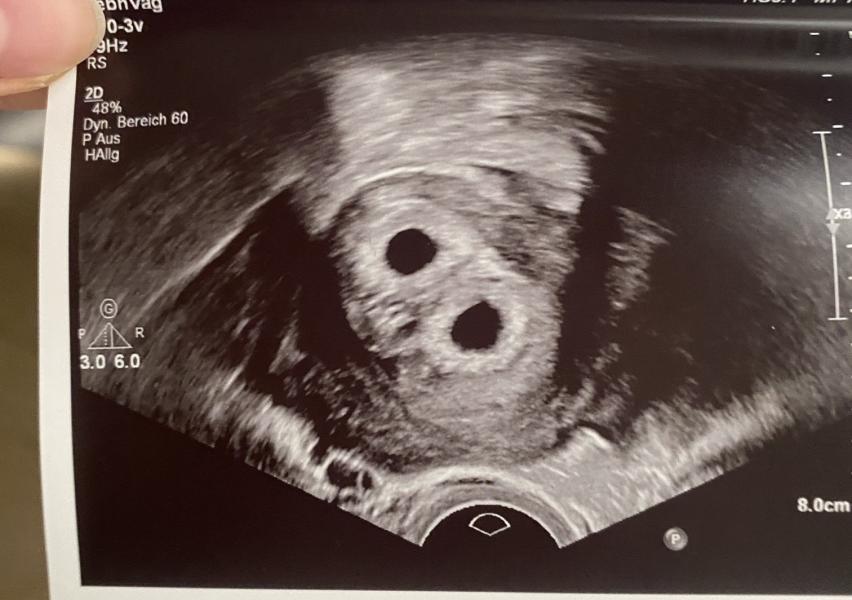

Ну что девочки, кто пророчил мне близнецов!? 😅 оказывается на 5 неделе ещё не было видно и у меня настоящая двойня, каждый в своём плодном мешочке. Я очень рада🙈 с близнецами много осложнений😫 а у двойни у каждого своя плацента и могут быть разнополые ❤️❤️❤️🥳

Да, написали что по снимку 100% близнецы, но врач мне тогда сказала что ещё рано что бы точно понять, но я уже подумала что раз два желточных мешочка в одном то точно близнецы. А это просто кадр был сделан таким образом, по другому врачу не могла сфоткать. И вот наконец-то на 6 неделе видно что двойняшки 😁🥳